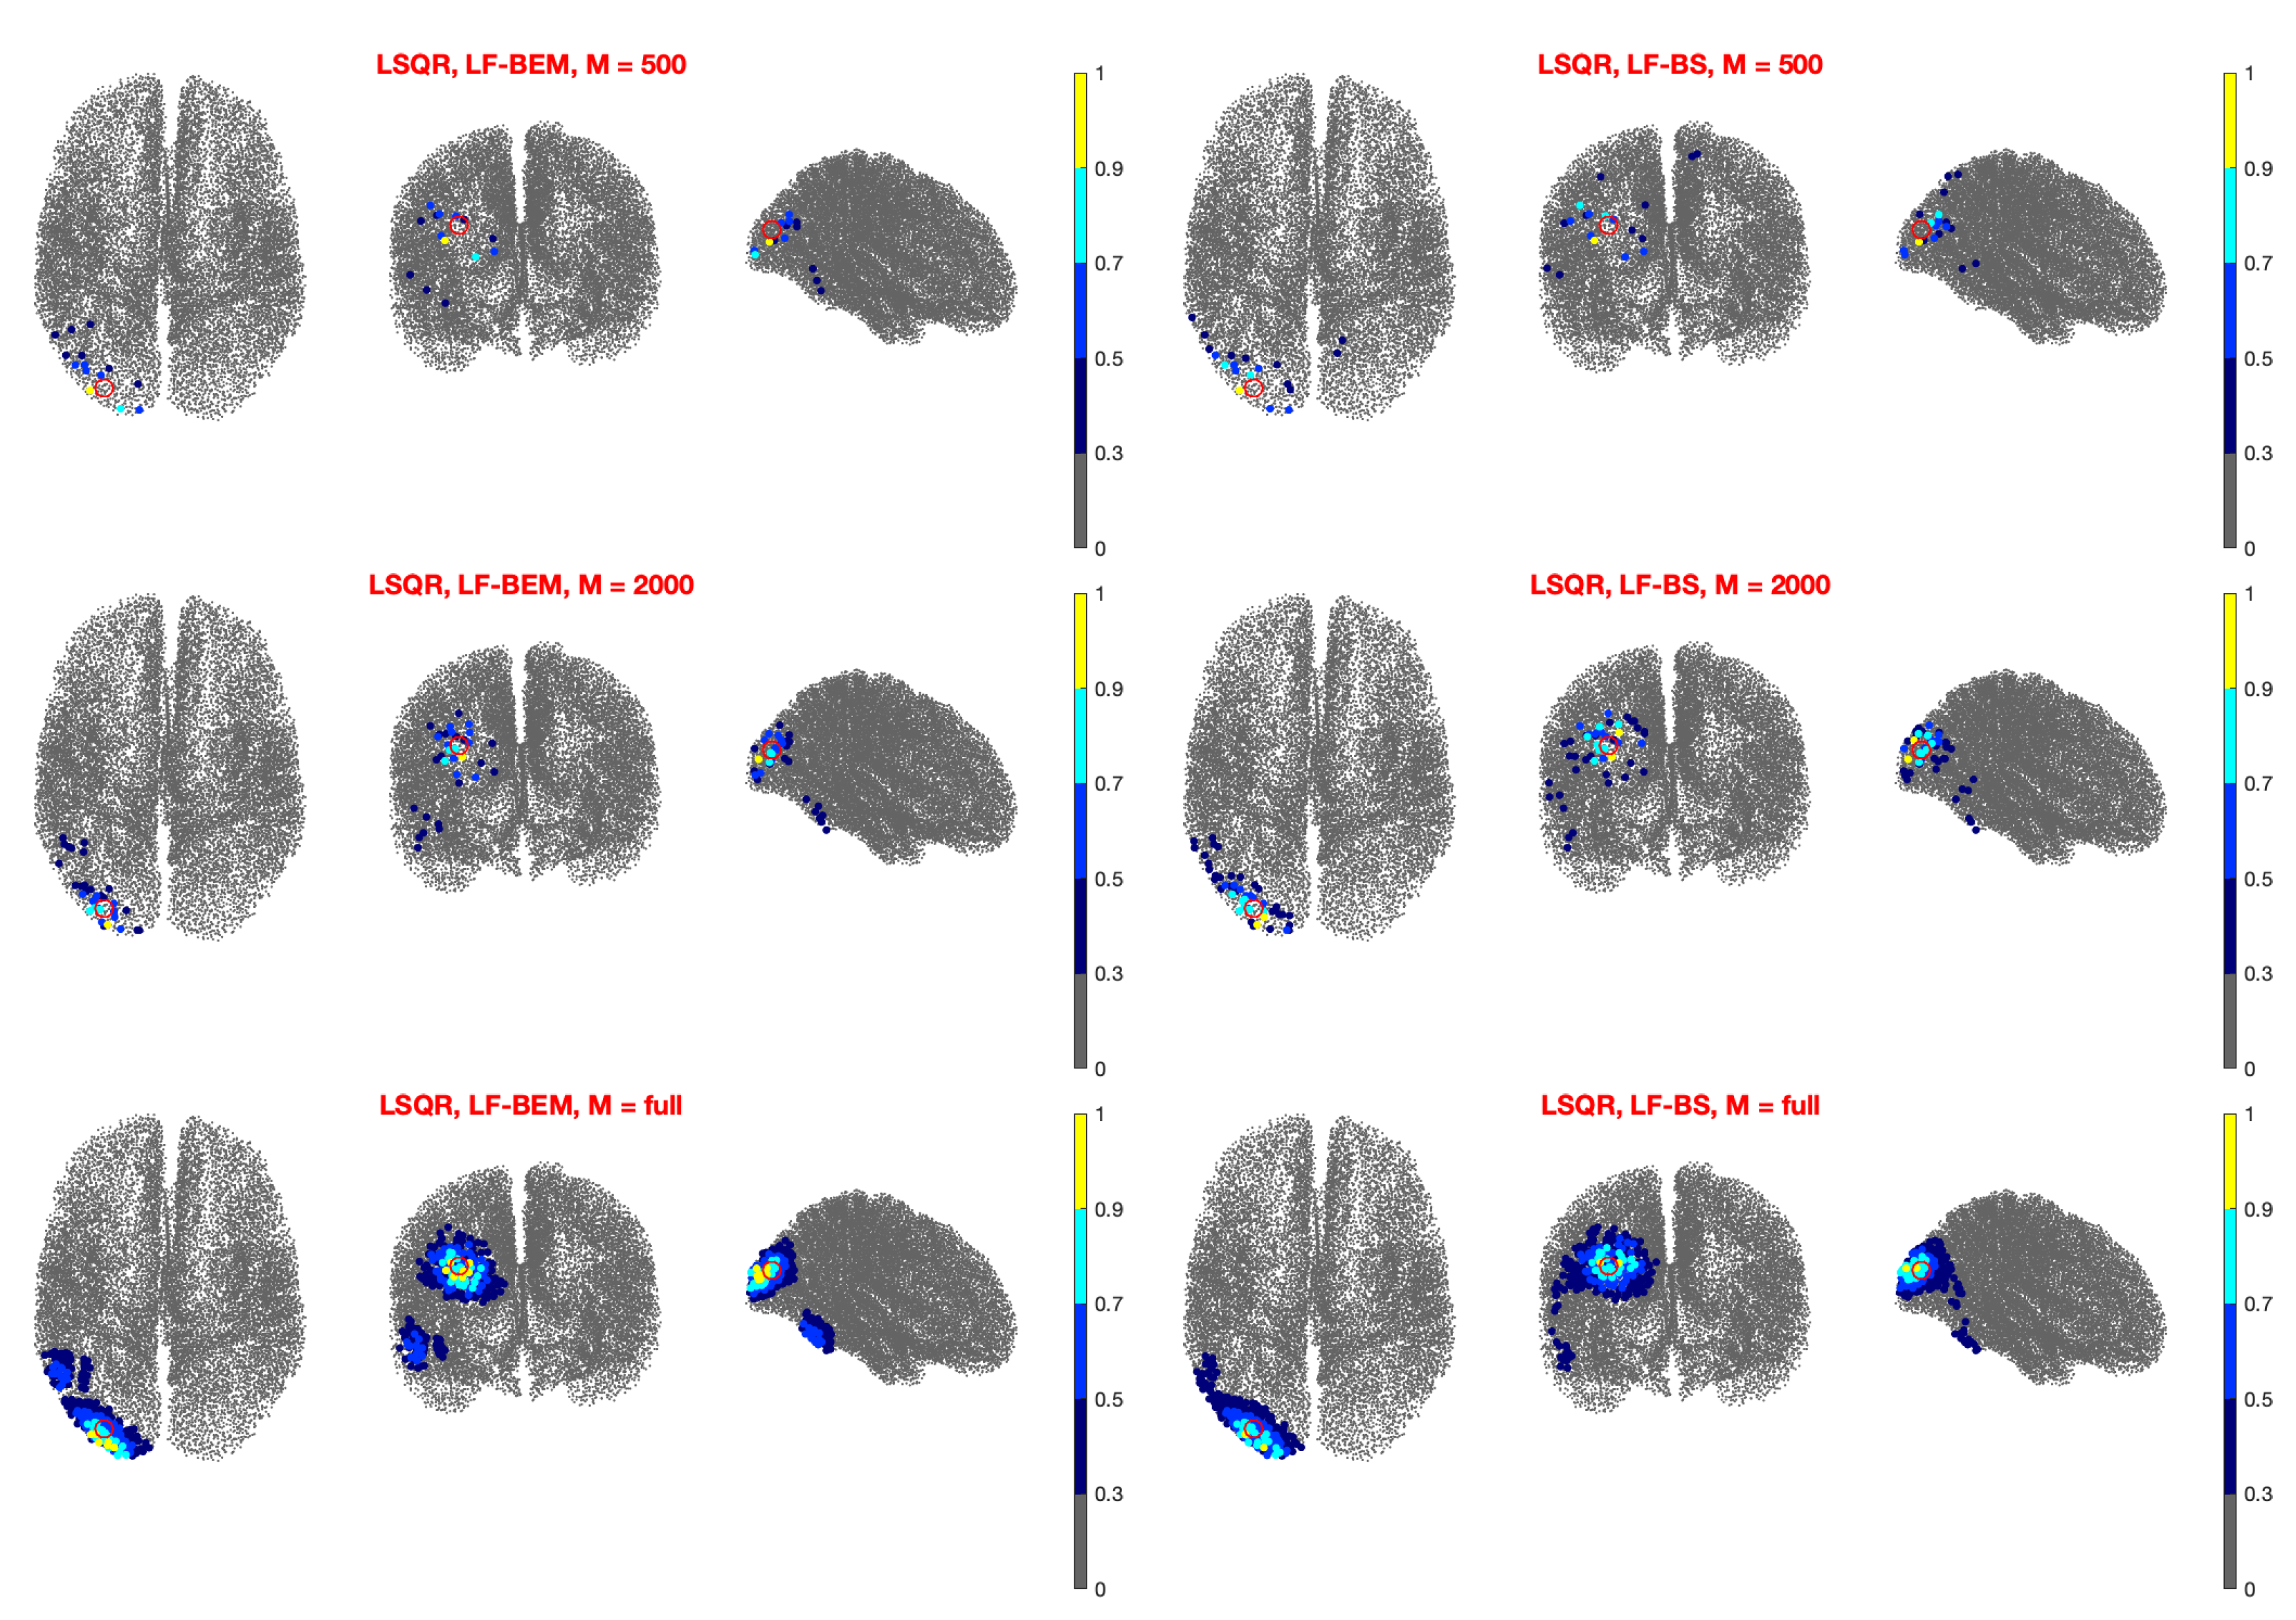

3.2. Real Data Analysis

- Left Auditory Case (Figure 2): The random sampling method with gives lower errors when using LCMV or TSBF as inversion methods. In particular, for the DLE is about 1 cm or less when they are coupled with LF-BS. As for the other inversion methods, LSQR produces a slightly higher DLE, i.e., below 2 cm, while wMNE and dSPM produce a DLE greater than 2 cm. As expected, the DLE decreases when M increases except for wMNE, which is the less accurate inversion method. Nevertheless, the decrease is very small for .